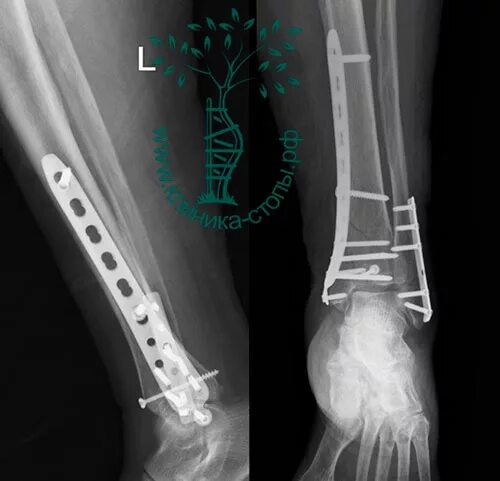

Перелом берцовой кости как разработать